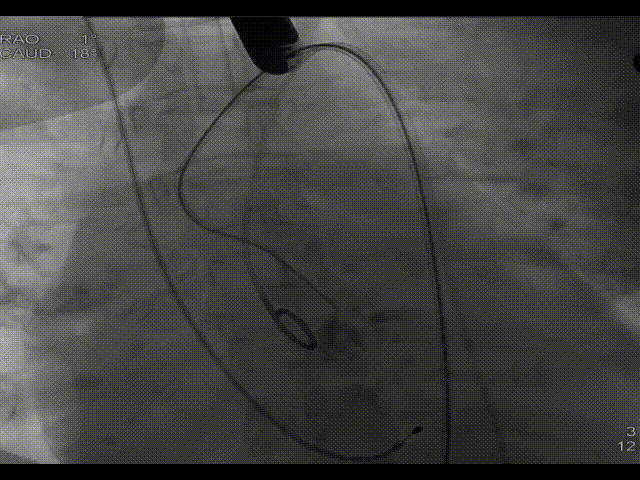

左冠造影及保护

20mm球囊预扩,无漏,冠脉灌注良好

TaurusOne释放过程

食道超声辅助瓣膜定位

瓣膜完全释放

造影显示瓣膜形态欠佳

22mm球囊后扩

造影显示形态显著改善,微量瓣周漏